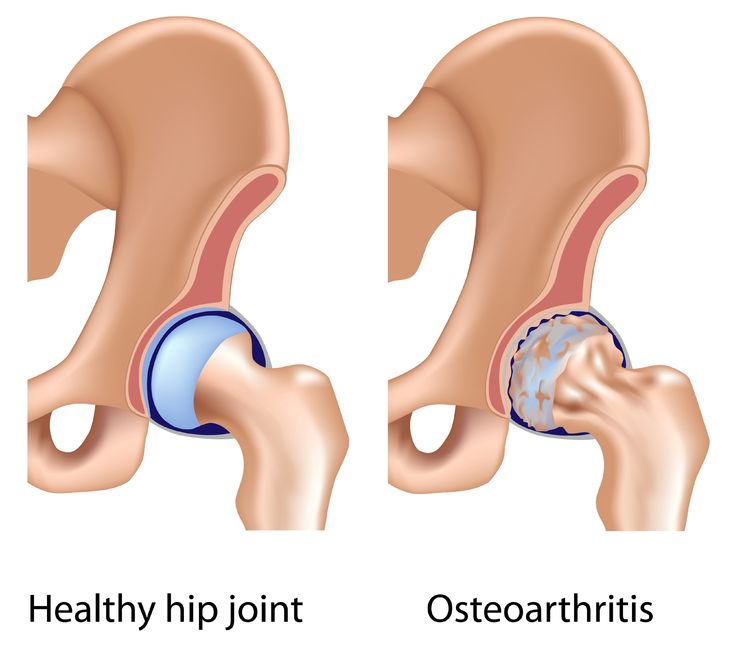

As with other types of arthritis, women are at higher risk than men for the condition. Osteoarthritis affects structures throughout the joint. Among them the cartilage, the slippery tissue that covers the ends of bones in a joint, is usually affected. Healthy cartilage allows bones to glide over one another and absorbs energy from the shock of physical movement.

In osteoarthritis, the surface layer of cartilage breaks down and wears away, which allows bones under the cartilage to rub together. This causes bone remodeling and change in boney shape and loss of motion of the joint. Over time, the joint loses its normal shape. Also, bone spurs—small growths called osteophytes—may grow on the edges of the joint. By the time a person has symptoms from osteoarthritis, it is no longer just a disease of cartilage. Bone has changed, muscles across the joint have often weakened and there is occasionally inflammation in the lining of the joint.

Osteoarthritis can occur in any joint but most often occurs at the joints in the hands, hips and knees.

- Hips: Osteoarthritis in the hip can cause pain, stiffness and severe disability. People most often feel the pain in their groin, front of thighs or knees. Walking aids, such as canes or walkers, can reduce stress on the hip. Osteoarthritis in the hip may limit moving and bending. This can make daily activities such as dressing and foot care a challenge. Walking aids, medication and exercise can help relieve pain and improve motion. A health care professional may recommend hip replacement if the pain is severe and not helped by other treatments.

- Osteoarthritis occurs when the surface layer of cartilage—the protective tissue between bones at joints—breaks down and wears away. This allows bones under the cartilage to rub together, causing pain, swelling and loss of motion of the joint.

- What causes osteoarthritis?In osteoarthritis, the surface layer of cartilage breaks down and wears away. This allows bones under the cartilage to rub together, causing pain, swelling and loss of motion of the joint. Major injuries to the joint, like tears of ligaments or of the meniscus in the knee, can also lead to osteoarthritis.